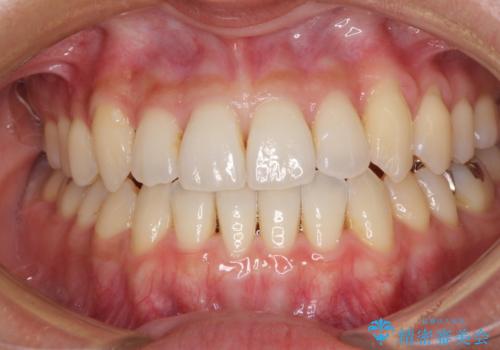

前歯のデコボコ インビザラインによる矯正治療

- 上下前歯の叢生と奥歯の反対咬合を気にして来院された患者様です。

インビザラインを用い、下顎はIPR(歯と歯の間を削る)と歯列全体を後方に移動させ、上顎は側方に拡大させることで歯列を改善していくこととしました。

骨格的に下顎が左側前方にずれているため、上下正中のズレや左右奥歯の咬み合わせを理想的な状態とすることは困難でした。